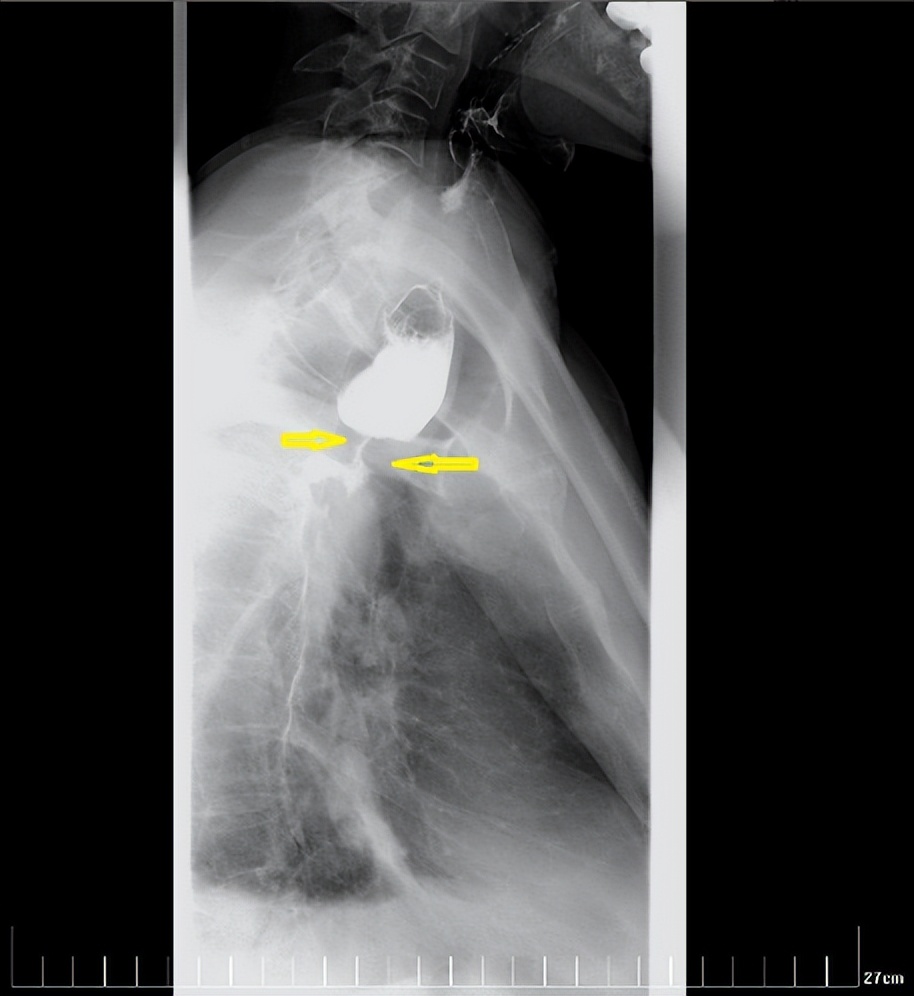

经过一个周期的放疗,李先生明显感受好多了,可以正常吃饭喝水。食管钡餐造影显示,食管吻合口区肿块明显缩小,食管狭窄减轻。

治疗前